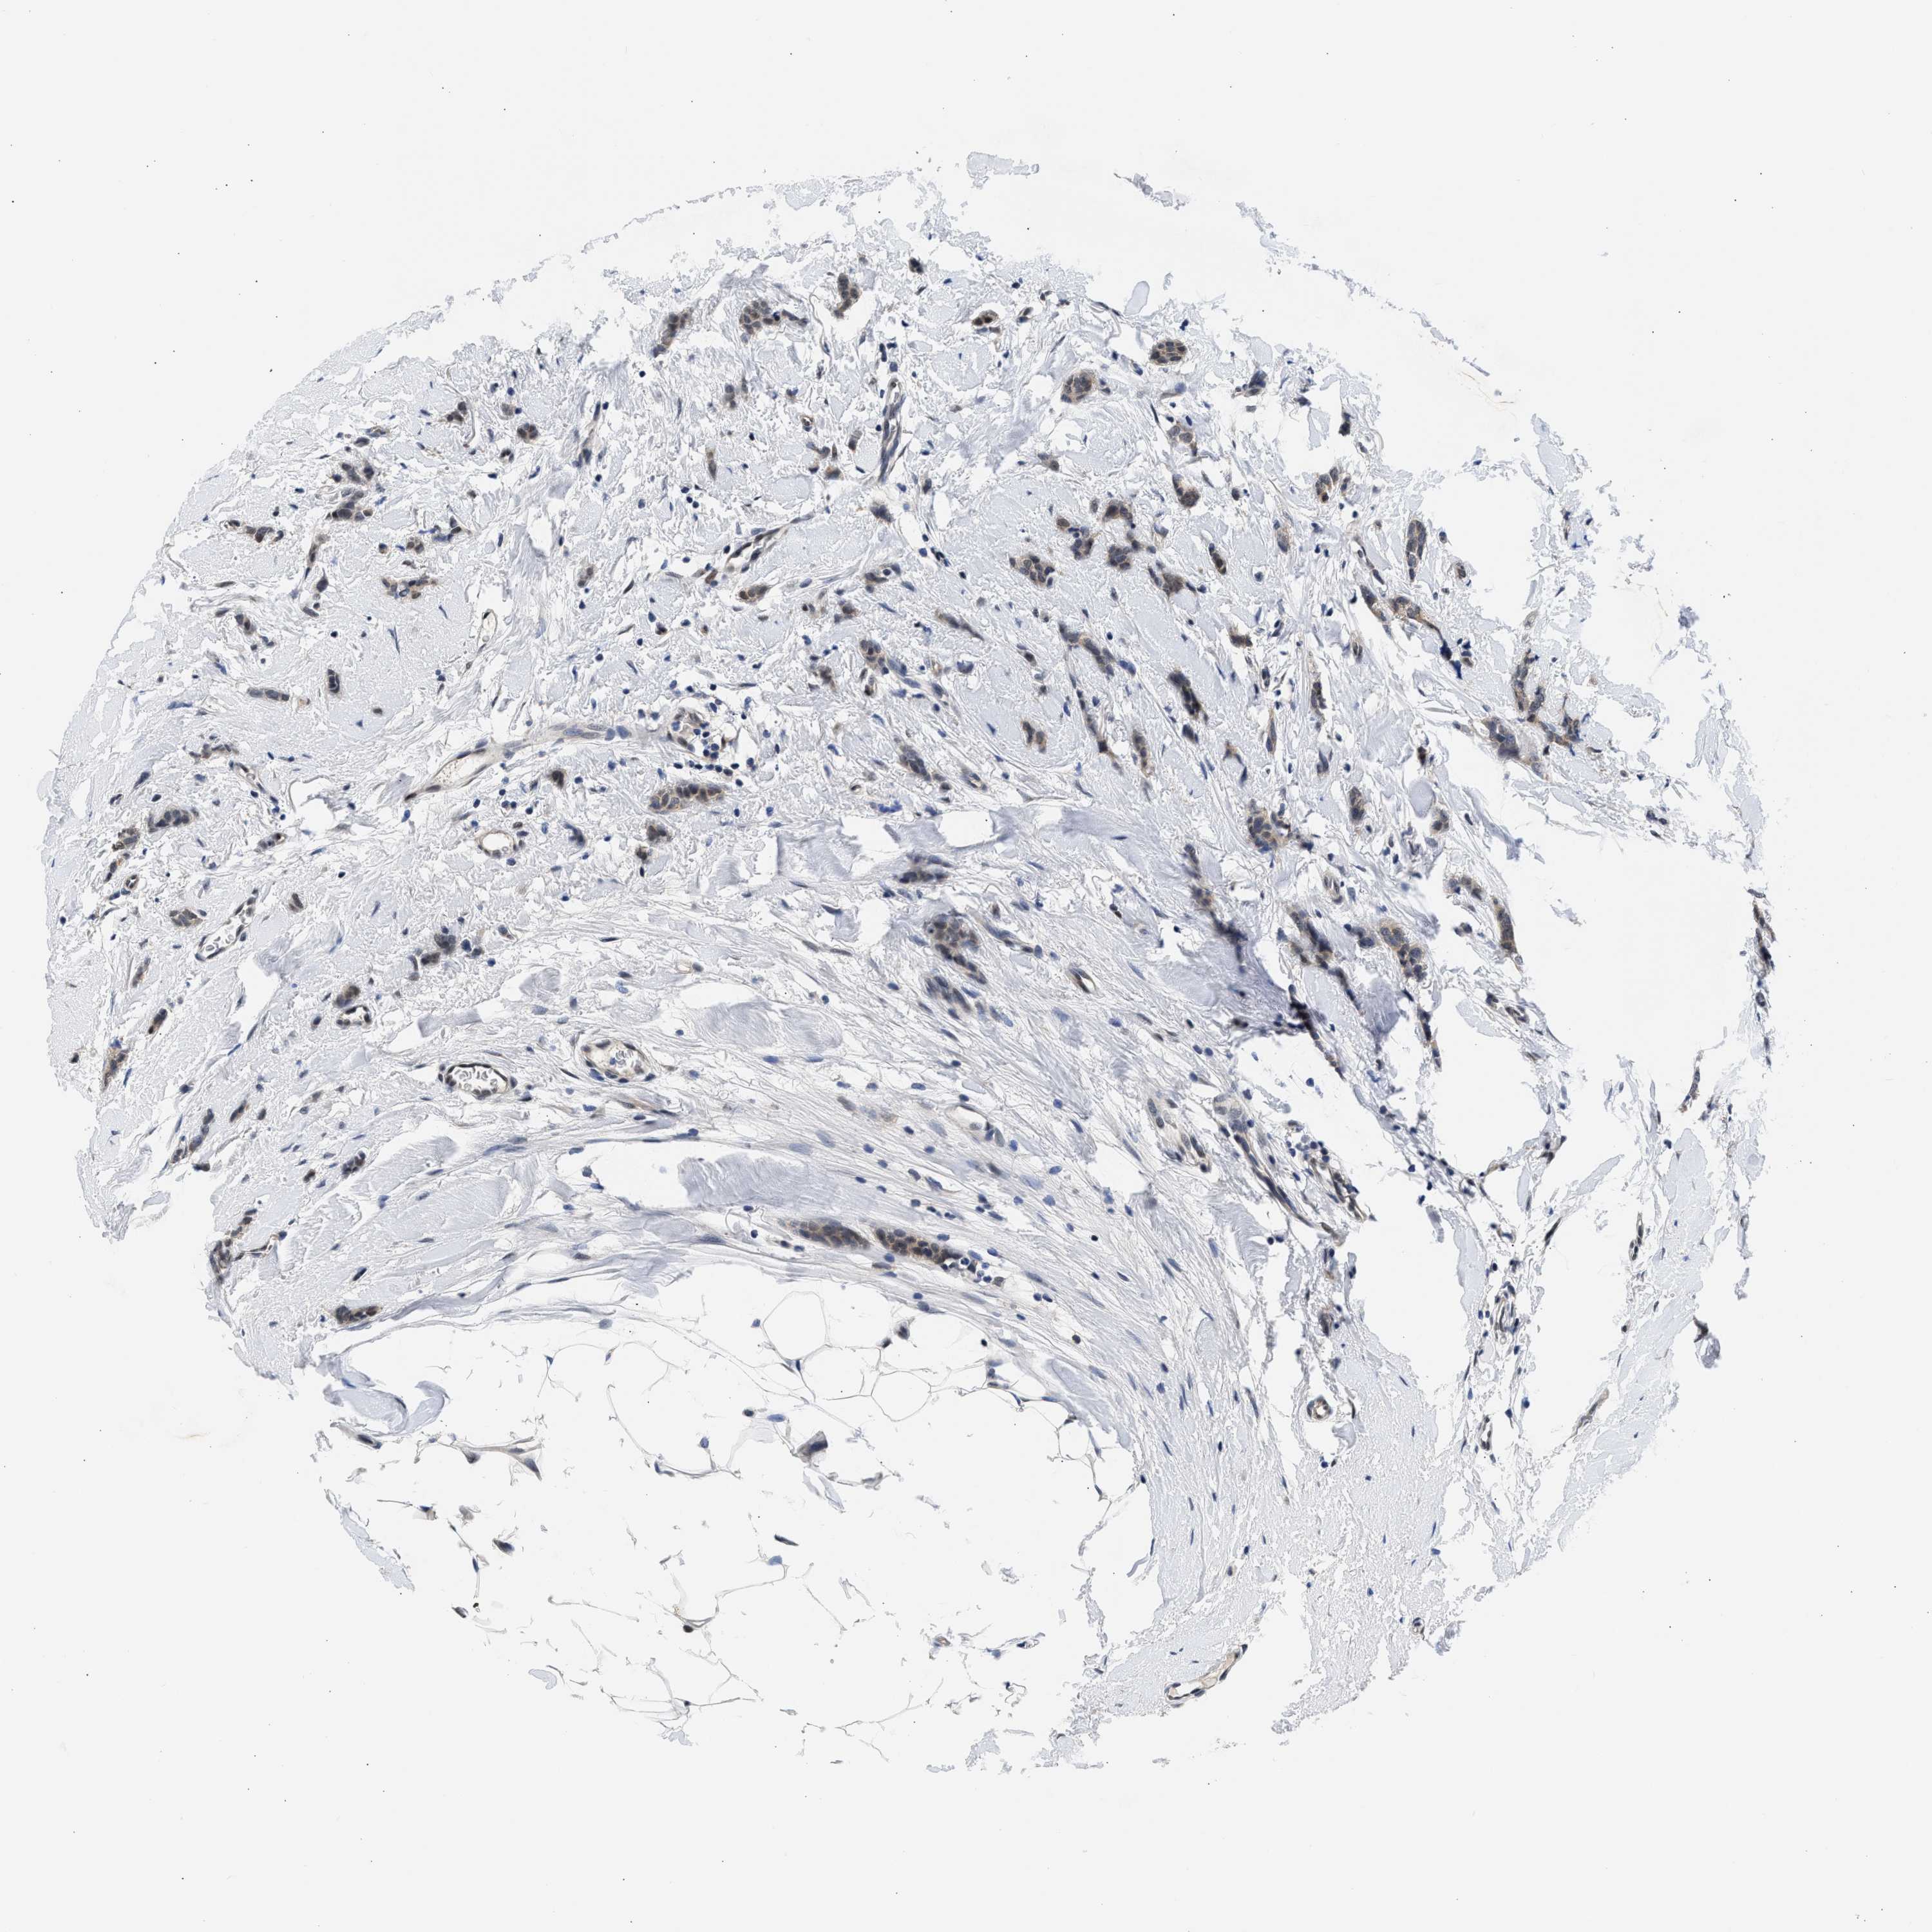

CANCER BREAST CANCER Show tissue menu

BRCA TCGA BRCA VALIDATION PROTEIN EXPRESSION